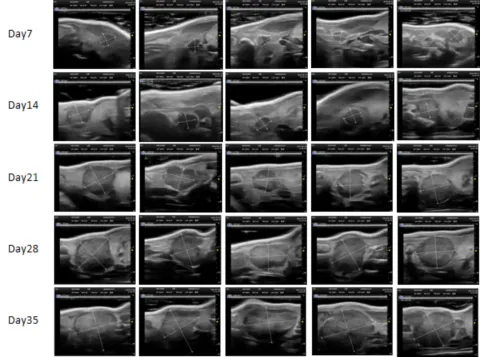

PDX Model (Growth Curve)

部分beats365PDX原位模型展示

部分beats365PDX原位模型展示